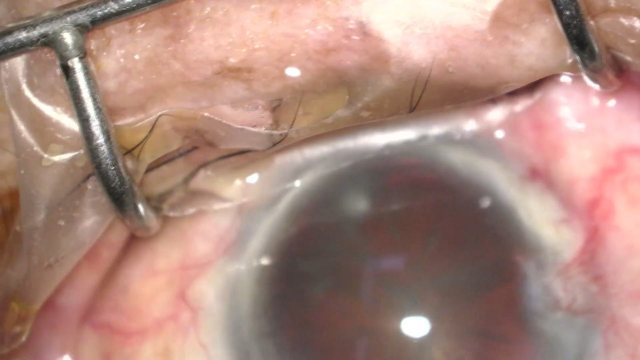

号外号外,湖南省人民医院副院长祖雄兵和眼科主任医师曾琦被指存在不正当关系,并有不雅视频传出。对此,医院工作人员回应:组织正在调查,请给医院宣传部门联系。当地卫生健康委员会对此回应:暂未接到相关的信访反映。祖雄兵为湖南省人民医院副院长,泌尿外科学科带头人。曾琦,博士,主任医师,硕士研究生导师。现任湖南省人民医院眼科副主任、眼科一病区主任,湖南省卫生健康高层次青年骨干人才,湖南省预防医学会眼病防治专业委员会主任委员、湖南省女医师协会眼科专业委员会主任委员、湖南省医学会眼科学专业委员会防盲学组副组长、湖南省医学会眼科学专业委员会眼外伤及职业病学组副组长、湖南省医学会眼科学专业委员会白内障学组副组长、